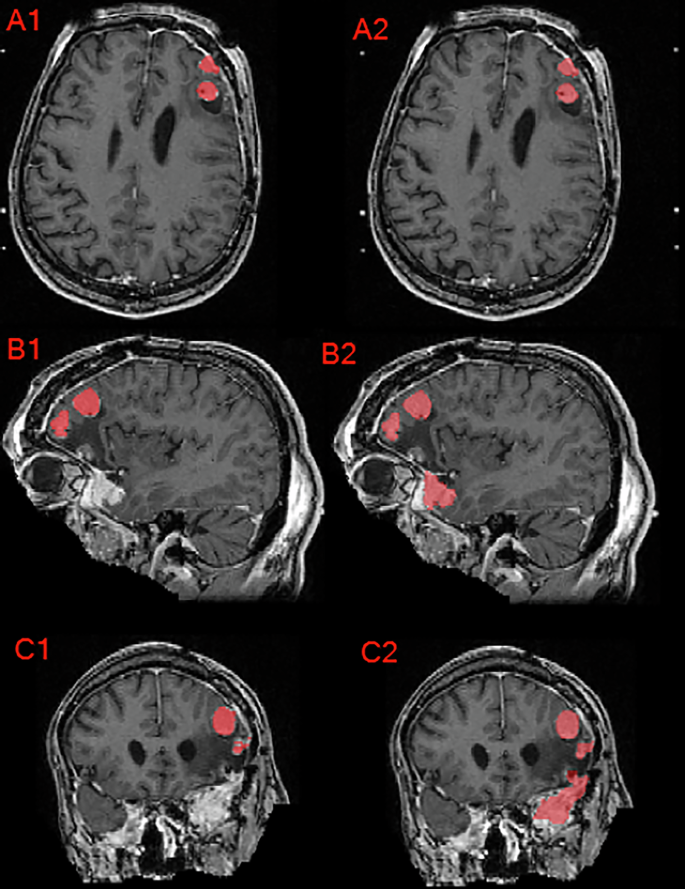

Axial, sagittal, and coronal brain MRI of a patient with multiple meningioma demonstrating the difference between the provided institution’s GTV as seen in panels A1, B1, and C1 compared to the manually revised target label as seen in panels A2, B2, and C2. Note that this case’s corrections involved inclusion of additional meningioma, correction of label edges, and inter-axial slice label smoothening.